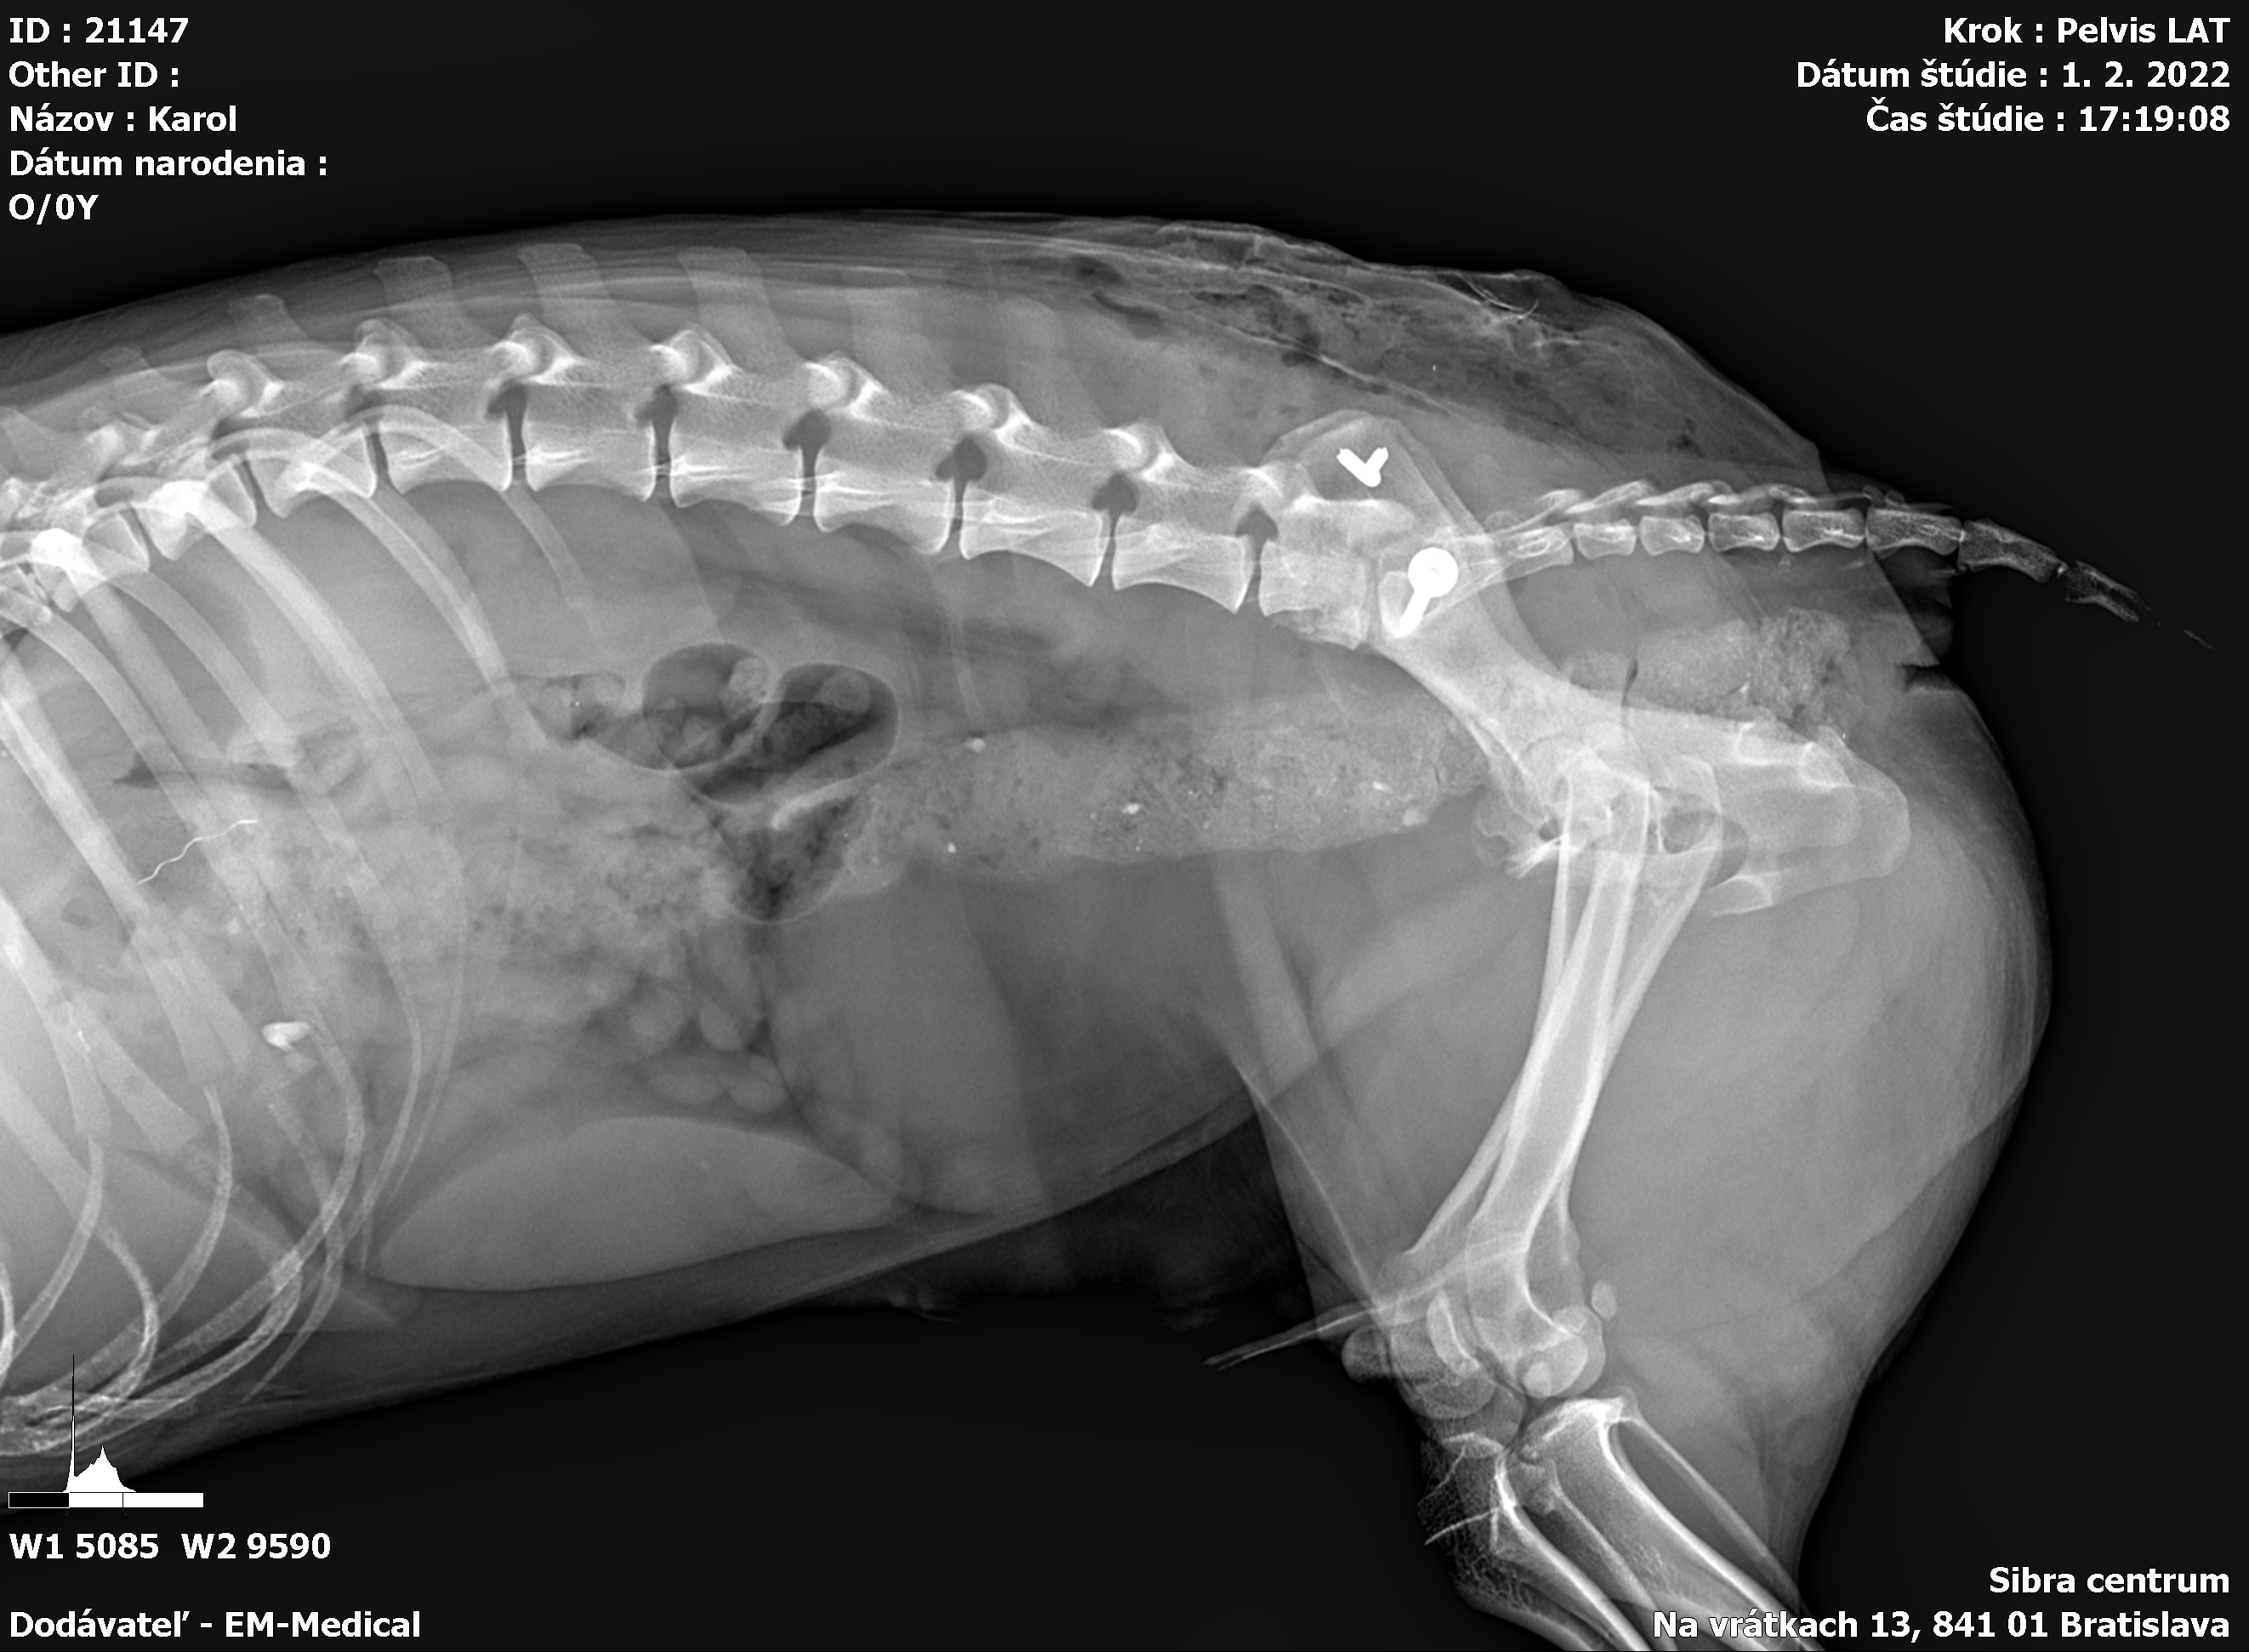

Karola nám doviezla pani, ktorá ho našla, asi jediná dobrá duša, ktorá pri ňom neprešla so zatvorenými očami. Ihneď sme s krpcom utekali na veterinu aby sa zistila závažnosť jeho zranení. Hneď pri prvých RTG snímkoch sa ukázala obojstranná fraktúra panvy, taktiež fraktúra krídla panvy a keby mu to chudákovi nestačilo, do tretice sa objavila zlomenina stavca. Karolko mal neznesiteľné bolesti, ale krásne prečkal vyšetrenie lebo vedel, že je v dobrých rukách a dostáva sa mu pomoci. Po nálezoch sme okamžite kontaktovali neurológiu a ortopédiu na veterinárnej klinike Sibra - centrum veterinárnej medicíny, kde sme dostali hneď termín na príjem.

Karol nemá žiadne neurologické deficity, po ortopedickej operácii bude vedieť behať a bez problémov bude vedieť samostatne cikať a kakať. Po tejto úžasnej správe sme samozrejme dali zelenú náročnej ortopedickej operácii pod vedením MVDr. Vatolíka. Operácia sa podarila na výbornú, Karči je "zoskrutkovaný" a vôbec nič mu nebráni v tom, aby opäť mohol behať a aktívne žiť. Momentálne sa zotavuje po operácii, musí mať prísny kľudový režim. Po vybratí stehov ho čaká hydro- a fyzioterapia, ktorá mu pomôže postaviť sa na nohy. Je to bojovník, veľmi sa chce uzdraviť a v jeho očkách je dokonale vidieť, že už kuje plány čo všetko zameškané bude musieť dobehnúť.